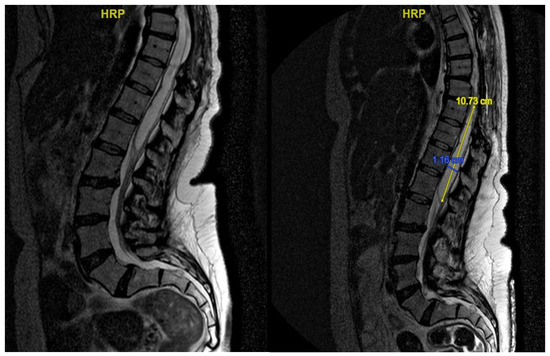

3.4.1. Case 1

| Level | T12–L2 | C5–C6 | T7–T10 | T8–T9 | T8–T11 |

| Location | Intramedullary | Intradural | Intradural–Extradural | Intramedullary | Intradural |

| Primary/secondary | Secondary | Secondary | Secondary | Secondary | Secondary |

| Surgical treatment | lysis of adherences and syrinx cavity opening | resection of the cystic formation and adhesiolysis | resection of the cystic formation and adhesiolysis | resection of the cystic formation and adhesiolysis | resection of the cystic formation and adhesiolysis |

| Complications | CSF fistula | infection | None | CSF fistula | None |

| KPS pre-op (%) | 70 | 50 | 70 | 80 | 90 |

| KPS post-op (%) | 80 | 50 | 60 | 90 | 80 |

| ASIA score pre-op | C | B | B | C | D |

| ASIA score post-op | D | B | C | C | D |